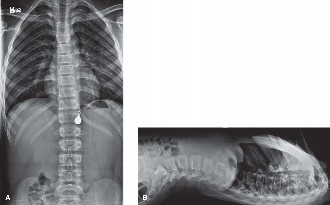

Plain Radiography Evaluation

The initial diagnostic modality consisted of standing full-length posteroanterior and lateral radiographs of the entire spine. The PA radiograph revealed a severe, short-segment, rigid dextroscoliosis centered at T8. The Cobb angle measured 52 degrees. The films clearly delineated a fully segmented T8 hemivertebra on the right (convexity) and an unsegmented osseous bar spanning from T7 to T9 on the left (concavity).

The lateral radiograph demonstrated a localized lordosis at the apex, confirming the three-dimensional complexity of the deformity. Supine bending films were obtained, which confirmed the absolute rigidity of the curve; the Cobb angle remained unchanged at 52 degrees on maximal side-bending. This rigidity is the pathognomonic radiographic signature of the unilateral unsegmented bar.